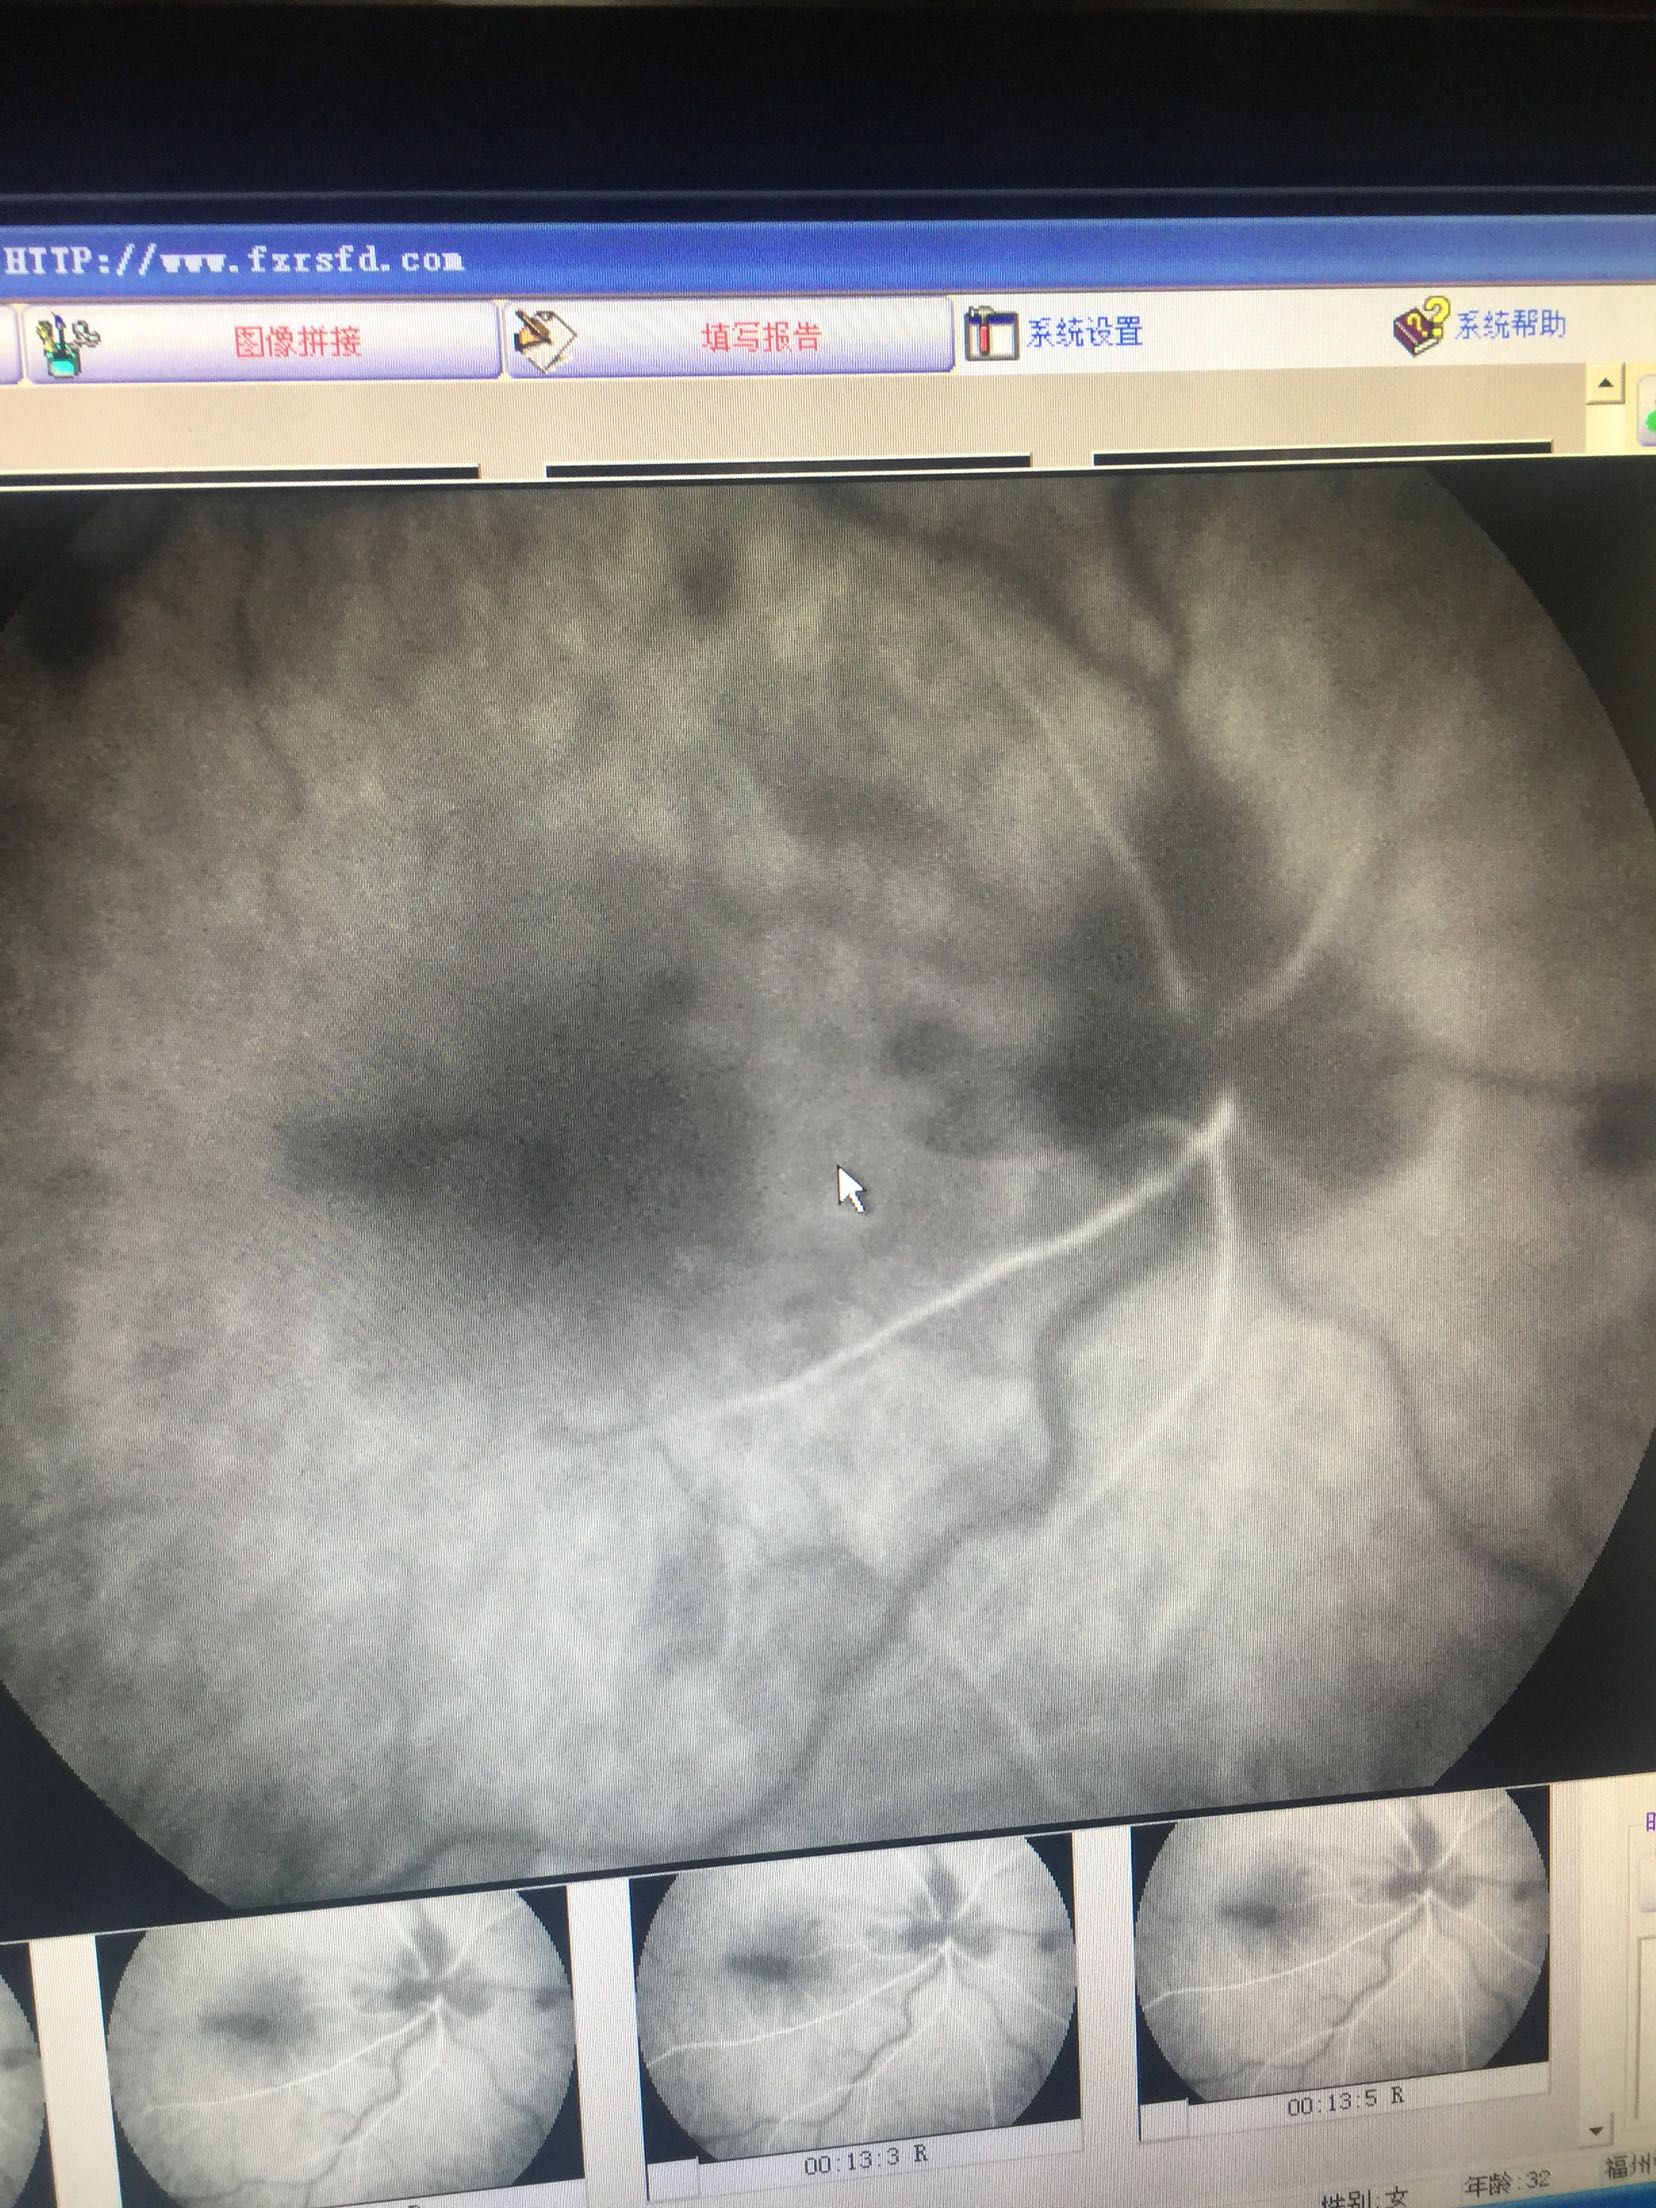

右眼:指数,左眼:0.15 双眼眼睑肤色正常,无红肿,结膜无充血,角膜透明,前房中深,瞳孔正大等圆,虹膜纹理清,晶体无浑浊,右眼眼底可见视盘出血水肿,边界不清,静脉迂曲扩张,黄斑区水肿出血,网膜散在片状出血,

右眼CRVO 扩张血管,营养神经治疗,眼底注射抗VEGF药

这种情况,很难有特别有效的预防手段,主要是规范生活习惯,避免劳累,饮食清淡。 眼底中央静脉阻塞引起的眼底出血,待出血吸收后,视力一般都会有进一步的提高的,但是要特别注意眼底新生血管增生的情况的,如果增生明显,会明显影响视力的,待出血吸收后,一定要做眼底造影明确的,必要时需要激光治疗的。